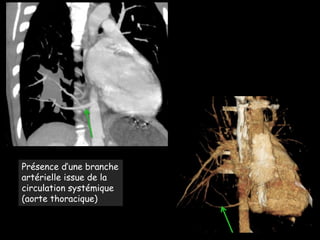

Présence d’une

branche

artérielle

issue de la

circulation

systémique

(aorte

thoracique)

Présence d’une branche

artérielle issue de la

circulation systémique

(aorte thoracique)